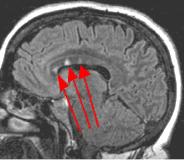

Fig. 3

Thin-section sagittal FLAIR images increase detection of small MS plaques even further, first reported by Hashemi, et al. (Ref. 1). They also have the advantage of clearly showing the corpus callosum and subependymal regions. An early sign of MS is subependymal nodularity and subcallosal striations (Ref. 1-2), not clearly visible on axial images. Fig. 3-4 in the same patient clearly show subcallosal MS plaques (arrows) along the undersurface of corpus callosum.